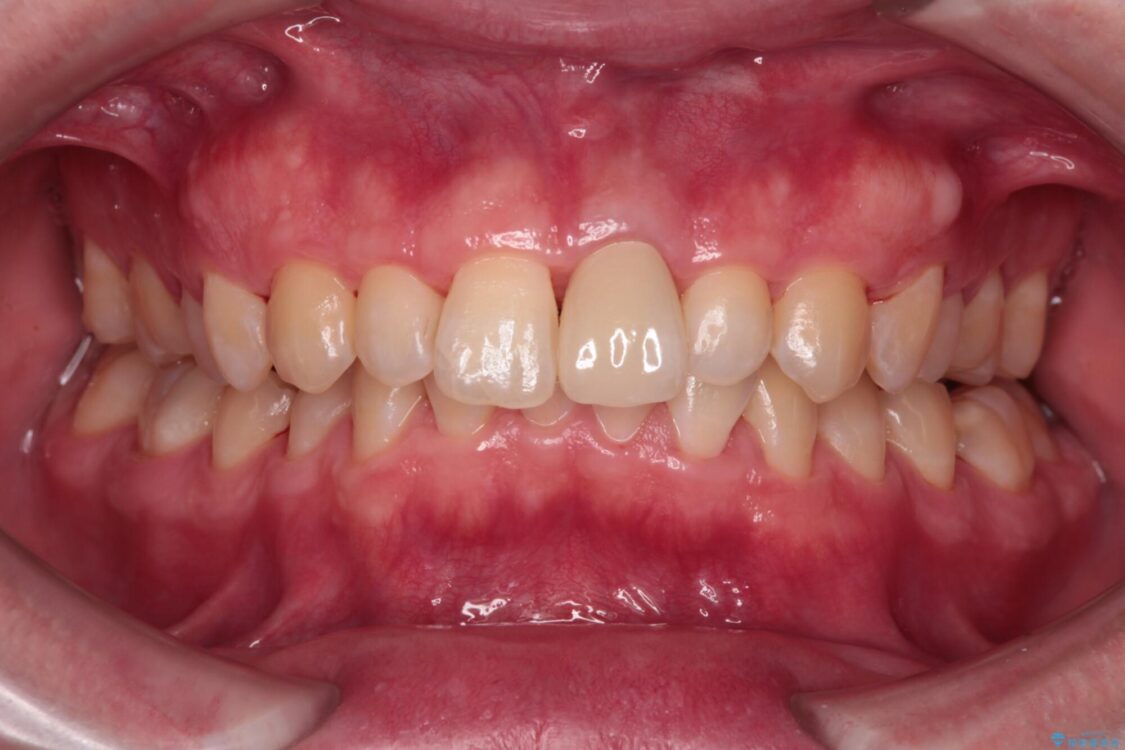

神経を取り除いたことで変色した前歯を気にして来院された患者様です。

根管治療はやり直さずに、ファイバーポストを使用した土台を植立してオールセラミッククラウンにて補綴することとしました。

治療前

• 変色した前歯をオールセラミッククラウンに 治療前画像